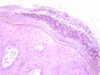

Histology showing which skin disease

Psoriasis